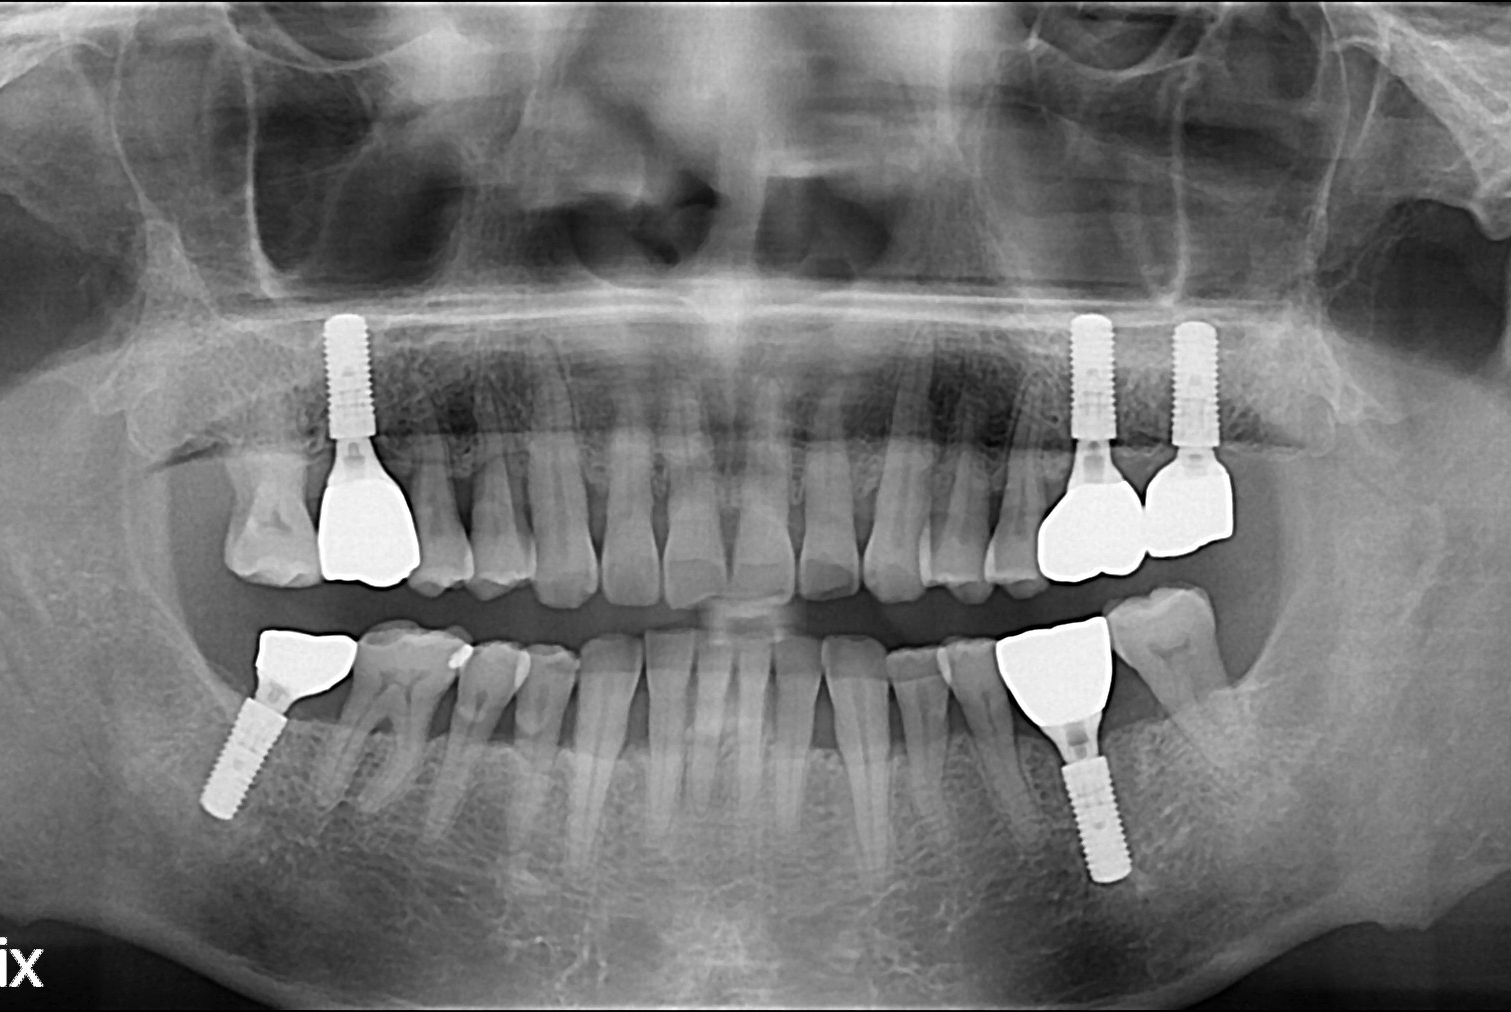

[임플란트] 임플란트

치료전 : 2018-09-13

세종치과는 많은 환자와 다양한 케이스를 바탕으로 항상 편안한 임플란트 수술을 제공하고자 노력하고,

오래동안 튼튼히 쓸 수 있는 임플란트 수술을 가장 큰 목표로 삼고 있습니다